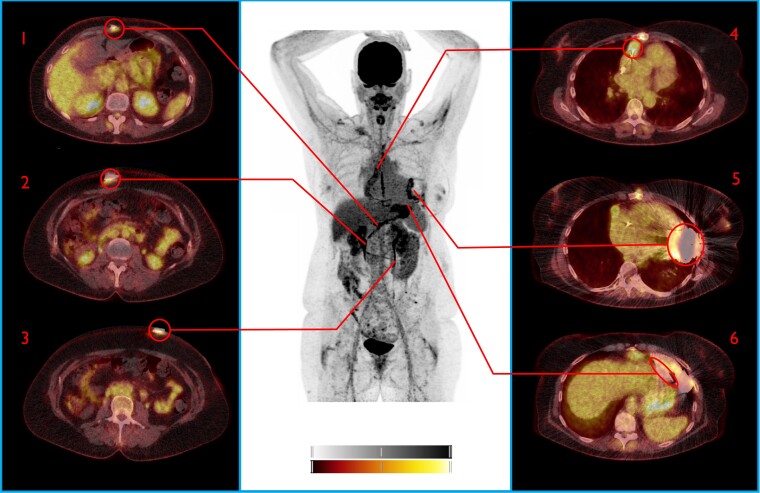

After manual delineation of volumes of interest (VOI), the maximum standardized uptake value (SUVmax) was measured at six predefined areas of interest in each patient. These regions comprised three areas alongside the peripheral driveline tract: driveline exit site, suprafascial driveline tract, and subfascial driveline, and three areas around the central device components: intrathoracic driveline, inflow canula/pump housing, and the outflow tract (Figures 1–3). Reference regions were manually drawn as spherical VOIs in the thoracic aorta and liver. The VOI in the aorta excluded the aortic vascular wall, and it was verified that the liver function tests were normal at the time of [18F]FDG PET/CT in the included patients.

Figure 3.

[18F]FDG PET/CT Driveline infection. Central device components false positive by visual analysis, true negative by SQ analysis. This patient presented with pain and discharge at driveline exit site, without further symptoms. FDFG uptake at driveline was homogenous and minimal, while central device components were FDG-avid, suspect for infection. Staphylococcus aureus was cultured from the driveline exit site and this was treated with oral antibiotics with good initial effect. Three months later, minimal surgical debridement of the driveline exist site was performed due to ongoing local irritation, still without any signs of systemic infection. A repeat [18F]FDG PET/CT 11 months after this episode showed an almost identical FDG uptake pattern around the central device component FDG uptake, confirming that this uptake was reactive. SUV ratio (liver/thorax) correctly identified this increased FDG uptake as too little to indicate infection. 1: Subfascial driveline, 2: Suprafascial driveline, 3: Driveline exit site, 4: Outflow tract 5: Pump housing, 6: Intrathoracic part driveline. NB: Note the increased FDG uptake around the driveline and the heterogeneous uptake around the pump housing and outflow tract (also visible on NAC images). Colour scales: 0–5 SUV.